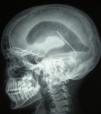

Pruebas complementarias: radiografía lateral de cráneo (fig. 1): neumoencéfalo en los ventrículos laterales (neumoventrículo) y VDVP. TC de cráneo (fig. 2): neumoventrículo con dilatación de los ventrículos laterales y VDVP.

La TC es una técnica diagnóstica muy sensible para realizar el diagnóstico y se considera el método de imagen de elección6 ya que es capaz de detectar cantidades de hasta 0,5ml de aire en la cavidad intracraneal7. En esta prueba el aire se observa como una imagen hipodensa redondeada, rodeada de parénquima cerebral normal. Un signo radiológico que ayuda a diagnosticar un neumoencéfalo a tensión es el signo de Monte Fuji, descrito como un ensanchamiento del espacio interhemisférico entre los lóbulos frontales8. En nuestro caso, el diagnóstico se hizo con una radiografía de cráneo solicitada dentro del estudio del trayecto de la VDVP.